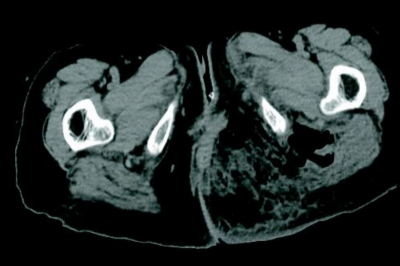

現症 : 意識レベルは JCSⅠ-2。身長 145 cm、体重 46.6 kg。体温 39.0 ℃。心拍数 92/分、整。血圧 108/76 mmHg。呼吸数 24/分。SpO₂ 98 %(マスク5L/分酸素投与下)。心音と呼吸音とに異常を認めない。腹部は平坦、軟で、肝・脾を触知しない。左殿部を別に示す。同部に強い圧痛を認める。内診で腟後壁に瘻孔と排膿が観察され、膿は悪臭である。直腸指診では異常を認めない。

殿部 CT の水平断像を別に示す。